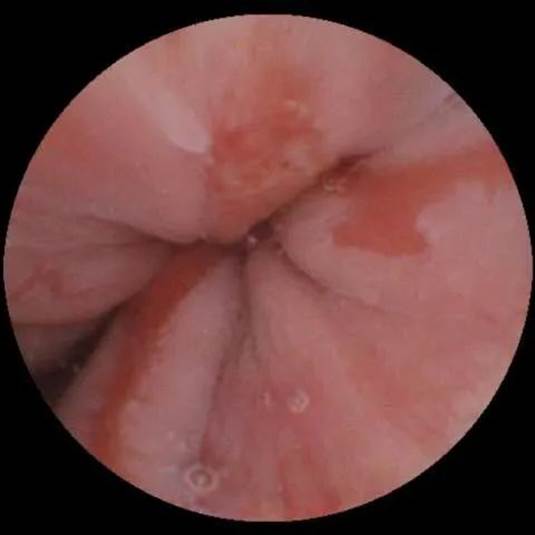

下面是磁控胶囊胃镜清晰地拍摄到“熬夜胃”受伤的模样。看了这些图片,你还会再熬夜吗?

病例1:反流性食管炎

病例2:胃糜烂

病例3:胃溃疡

病例4:胃癌